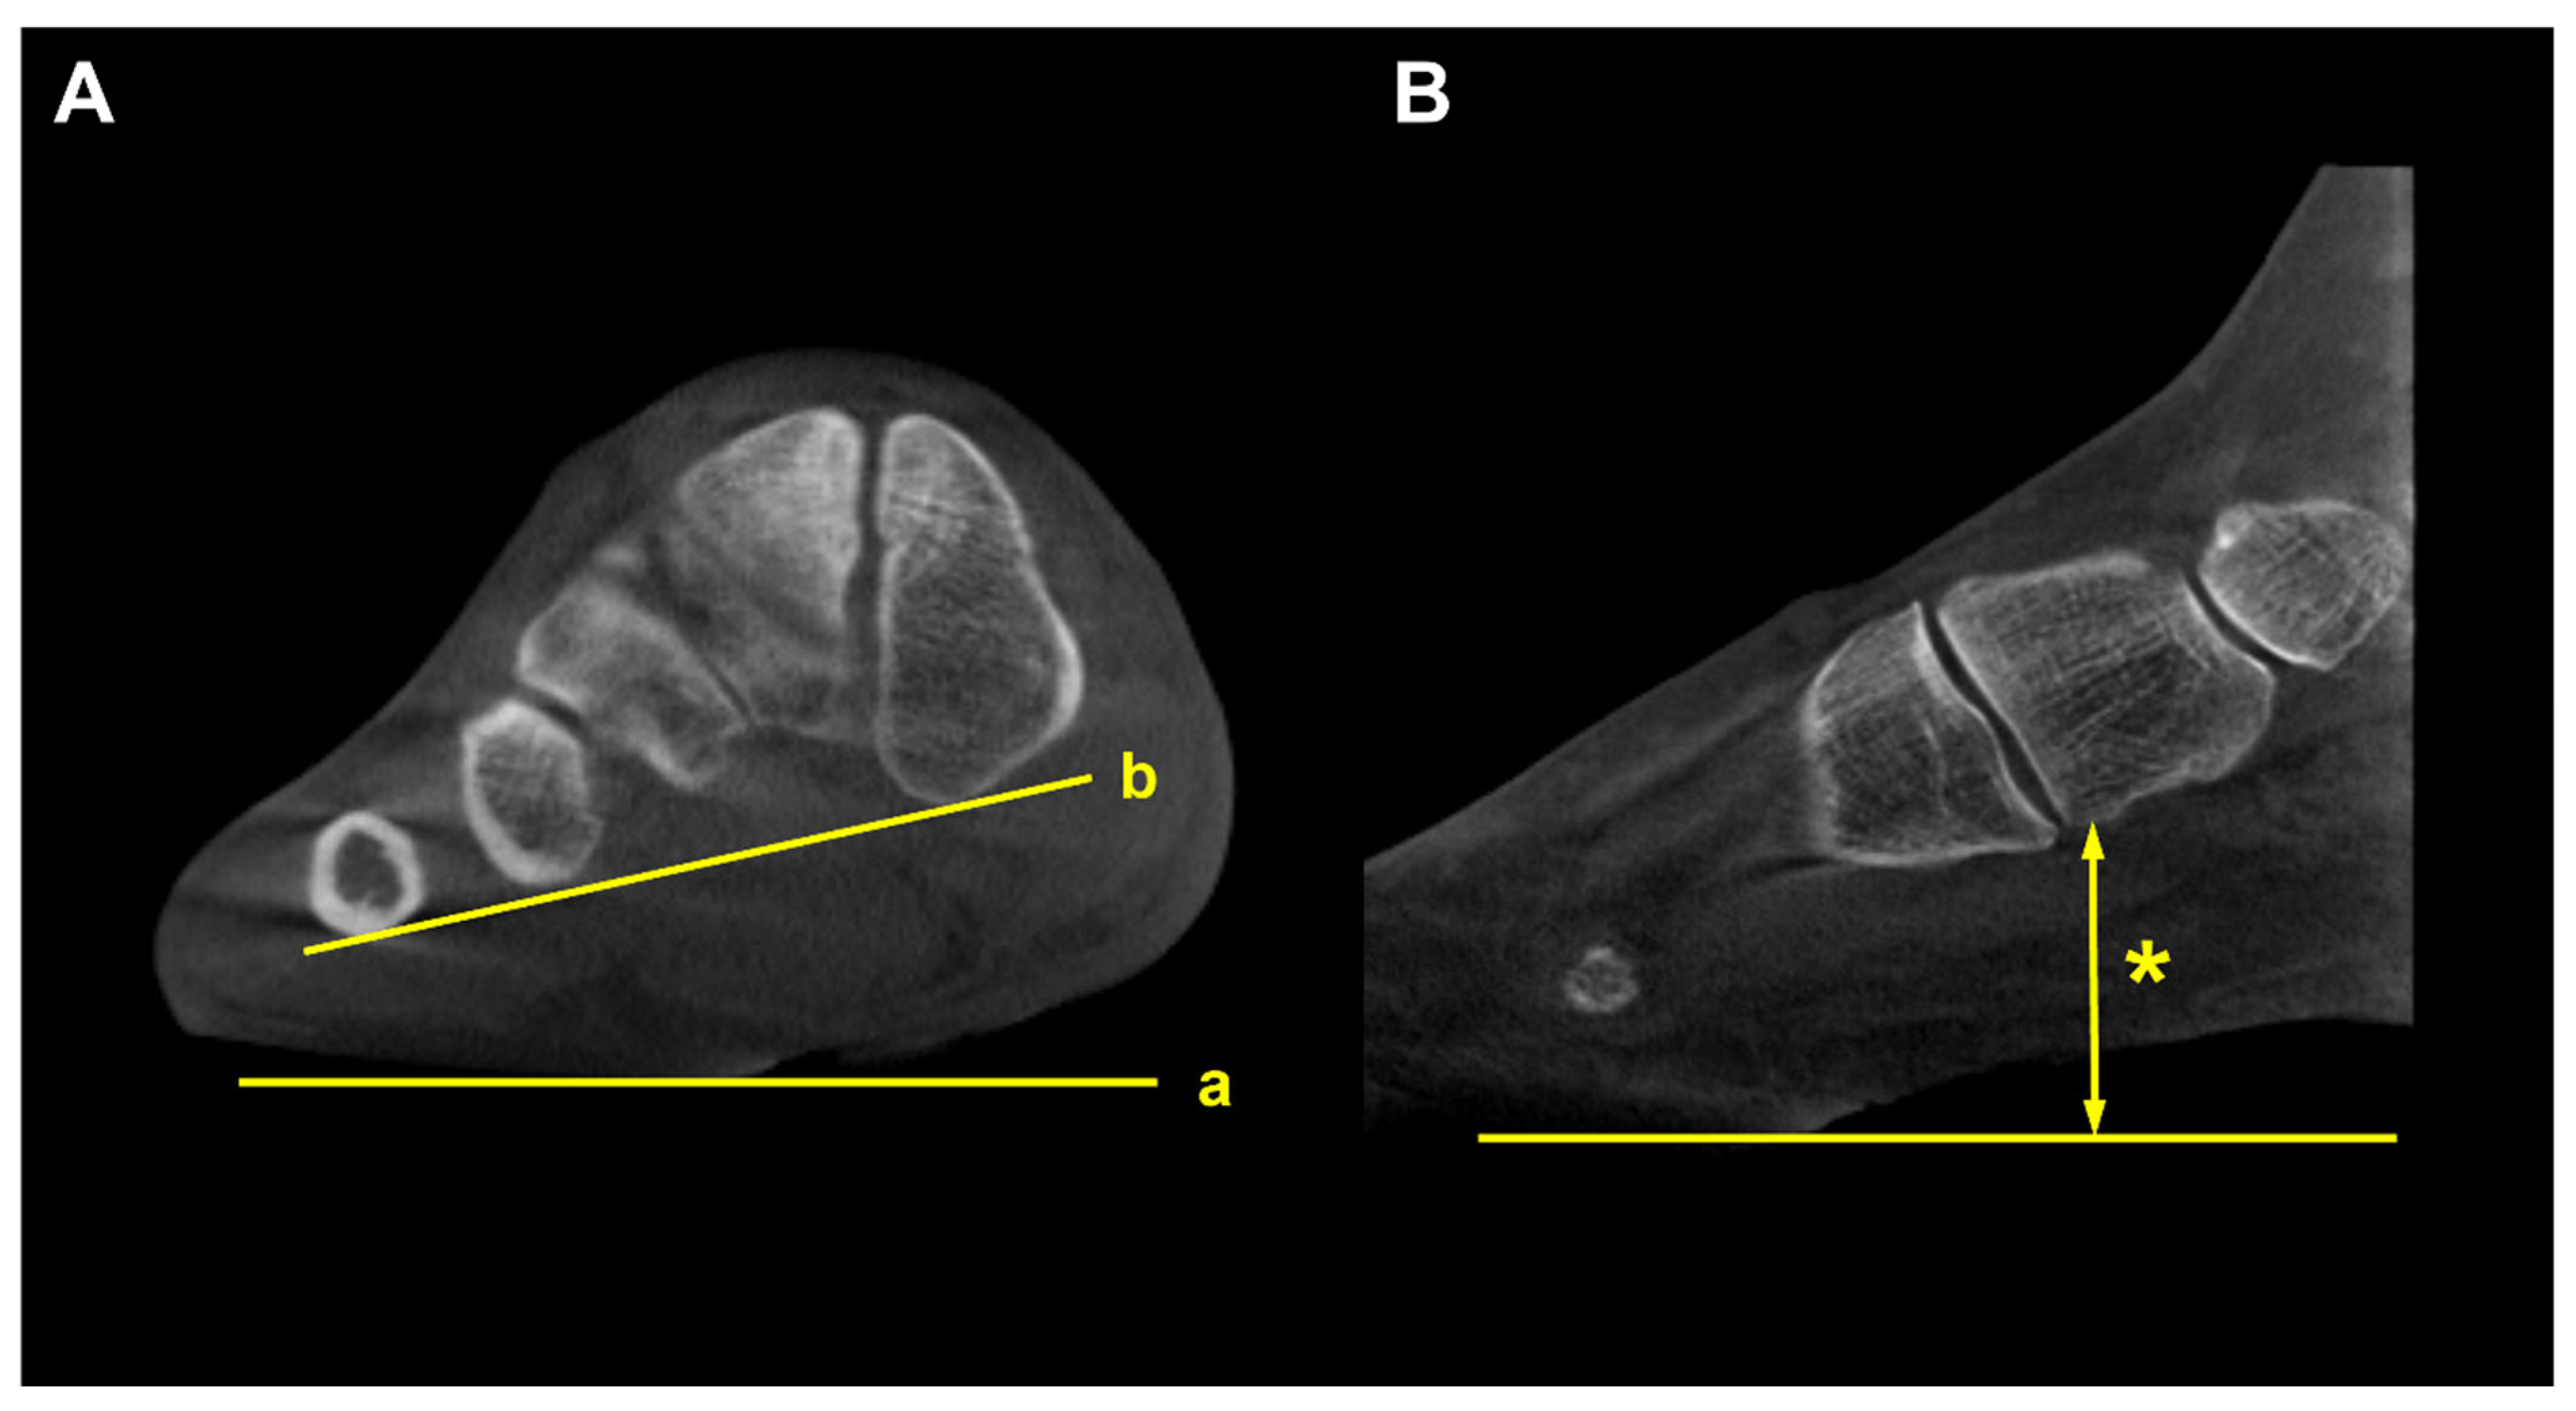

Figure 2. To obtain the alpha (α) angle, first, an inferior line is drawn between the lateral edge of the lateral sulcus and the medial edge of the medial sulcus (a). Subsequently, a superior line is drawn between the point of the medial and lateral corners of the first metatarsal head (b). Second, bisections of the above 2 lines are connected to a straight line perpendicular to the horizontal ground axis (c). Third, the angle is measured between the straight line (c) and the vertical line perpendicular to the ground axis (d) that is obtained from the first step.

Using a semi-weightbearing CT, Kim et al devised the alpha angle to evaluate the pronation of the M1 [11]. It was determined on the axial view by measuring the angle between the line bisecting the M1 and the vertical line perpendicular to the horizontal ground axis (Figure 2). Authors reported that 87.3% of the patients with hallux valgus had a more pronated M1 than the control group, with a greater alpha angle. Similarly, Campbell et al measured the M1 rotation with 3D geometrically determined angles and found that M1 pronation relative to second metatarsal was 8.2 degrees greater in the hallux valgus group than in the control group [12]. Furthermore, Mansur et al used WBCT to verify the round sign, an indirect sign of M1 pronation in conventional radiographs, and concluded that round sign weakly correlated with the alpha angle measured on WBCT [13]. Overall, these findings suggest that it is challenging to fully recognize the complex 3D deformities of hallux valgus using only conventional radiographs and incorporation of WBCT would be beneficial.

Several studies focused on the impact of M1 pronation after hallux surgery. Conti et al conducted a study to determine if postoperative decrease in M1 pronation observed in WBCT would be associated with changes in patient-reported outcomes [14]. Patients who underwent modified Lapidus procedure for hallux valgus were divided into two groups with regards to the amount of postoperative M1 pronation change, and the Patient Reported Outcomes Measurement Information System (PROMIS) scores were compared between groups. At 2 years postoperatively, patients who had significant decrease in M1 pronation after modified Lapidus procedure showed greater improvement in the PROMIS physical function domain. Choi et al utilized simulated weight bearing CT to evaluate the association between preoperative M1 pronation and postoperative recurrence after proximal chevron osteotomy [15]. To quantify the amount of preoperative M1 pronation, authors measured M1 pronation angle (M1PA) (Figure 3). They reported that patients who had significant correction loss at 1 year after surgery exhibited higher preoperative M1PA, with a 28.4 degrees threshold. These results pose an importance of recognizing preoperative M1 pronation through WBCT because rotational component of the hallux valgus deformity would impact postoperative outcomes and recurrence rates after surgery.

Figure 3. M1 pronation angle (M1PA) is the angle between the floor (a) and a line drawn from the most inferomedial border of the medial sesamoid facet to the most lateral border of the lateral sesamoid facet (b).